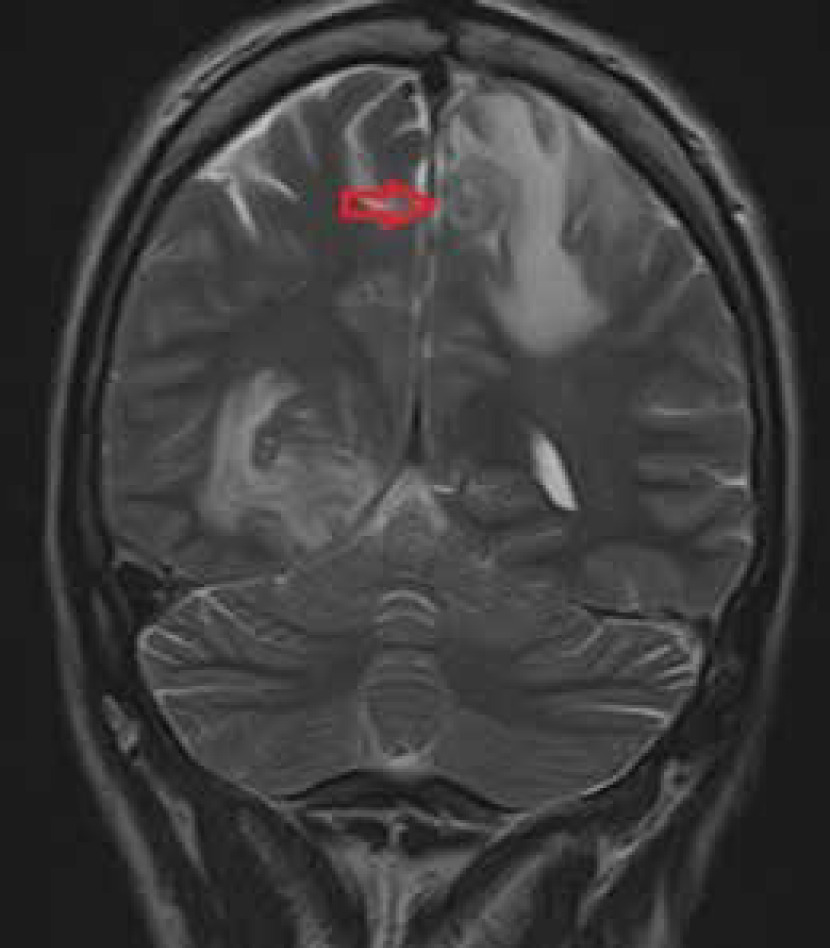

Mahadevan et al. presented a 40-year-old patient with a fever lasting for 7 days, infected with HIV. MRI showed numerous lesions, including in basal ganglia, as well as bilateral thalami and midbrain, frontal lobes (bilateral), and crus cerebri. Frontal lobe lesions were hypointense on T1-weighted images and hyperintense on T2-weighted images, accompanied by perilesional oedema, along with central hypointensity. The lesions in the caudate nucleus were ring-like and non-uniformly hyperintense at T1WI. In turn, the lesion involving bilateral thalamus – concentric target signal, seen in coronal T2WI, was visible as concentric layers of hypo- and hyperintensities with central hypointensities, surrounded by oedema, while in T1WI it was visible as a hypointense lesion. A similar change was also observed in left crus cerebri [29].

The presented cases show that the most frequent lesions imaged in MRI are located in the basal ganglia and frontal lobes. Most lesions enhance after administration of contrast, most often appearing ring-shaped. The enhancement may not be noticed in patients who are taking immunosuppressive drugs. In both post-contrast T1WI and T2WI, characteristic signal (eccentric and concentric) of TE can be found; however, they are not always visible. Lesions in MR and their intensity may depend on the stage of disease development [43]. In response to treatment, the intensity of lesions seen in the T1 and T2 sequence decreased and shrank in size. Lesions often co-occur with oedema and a mass effect, seen in T2/FLAR sequences (Figures 1 and 2).